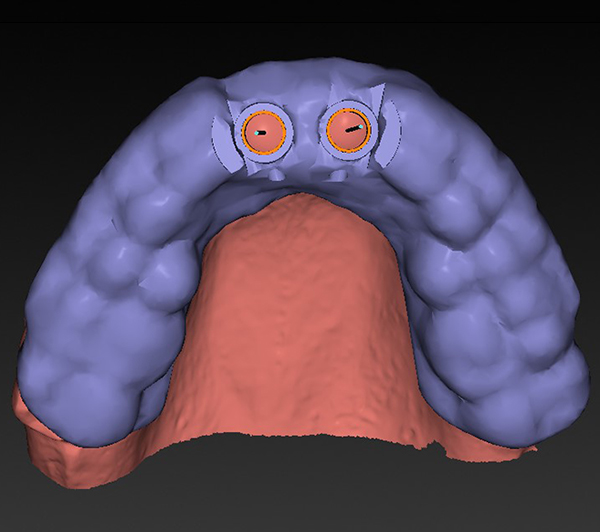

The special report presented below illustrates how orthodontic extrusion was successfully used to improve the periodontal architecture prior to the placement of two adjacent implants in the esthetic zone and thus allowed for a more ideal restorative result.